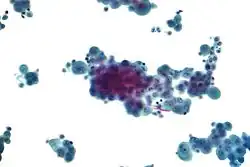

Imaging

Diagnosing mesothelioma is often difficult because the symptoms are similar to those of a number of other conditions. Diagnosis begins with a review of the patient's medical history. A history of exposure to asbestos may increase clinical suspicion for mesothelioma. A physical examination is performed, followed by chest X-ray and often lung function tests. The X-ray may reveal pleural thickening commonly seen after asbestos exposure and increases suspicion of mesothelioma.[15] A CT (or CAT) scan or an MRI is usually performed. If a large amount of fluid is present, abnormal cells may be detected by cytopathology if this fluid is aspirated with a syringe.[11] For pleural fluid, this is done by thoracentesis or tube thoracostomy (chest tube); for ascites, with paracentesis or ascitic drain; and for pericardial effusion with pericardiocentesis. While absence of malignant cells on cytology does not completely exclude mesothelioma, it makes it much more unlikely, especially if an alternative diagnosis can be made (e.g., tuberculosis, heart failure). However, with primary pericardial mesothelioma, pericardial fluid may not contain malignant cells and a tissue biopsy is more useful in diagnosis.[11] Using conventional cytology diagnosis of malignant mesothelioma is difficult, but immunohistochemistry has greatly enhanced the accuracy of cytology.

Biopsy

Generally, a biopsy is needed to confirm a diagnosis of malignant mesothelioma. A doctor removes a sample of tissue for examination under a microscope by a pathologist. A biopsy may be done in different ways, depending on where the abnormal area is located. If the cancer is in the chest, the doctor may perform a thoracoscopy. In this procedure, the doctor makes a small cut through the chest wall and puts a thin, lighted tube called a thoracoscope into the chest between two ribs. Thoracoscopy allows the doctor to look inside the chest and obtain tissue samples. Alternatively, the cardiothoracic surgeon might directly open the chest (thoracotomy). If the cancer is in the abdomen, the doctor may perform a laparoscopy. To obtain tissue for examination, the doctor makes a small incision in the abdomen and inserts a special instrument into the abdominal cavity. If these procedures do not yield enough tissue, an open surgical procedure may be necessary.

Immunochemistry

Immunohistochemical studies play an important role for the pathologist in differentiating malignant mesothelioma from neoplastic mimics, such as breast or lung cancer that has metastasized to the pleura. There are numerous tests and panels available, but no single test is perfect for distinguishing mesothelioma from carcinoma or even benign versus malignant. The positive markers indicate that mesothelioma is present; if other markers are positive it may indicate another type of cancer, such as breast or lung adenocarcinoma. Calretinin is a particularly important marker in distinguishing mesothelioma from metastatic breast or lung cancer.[12]